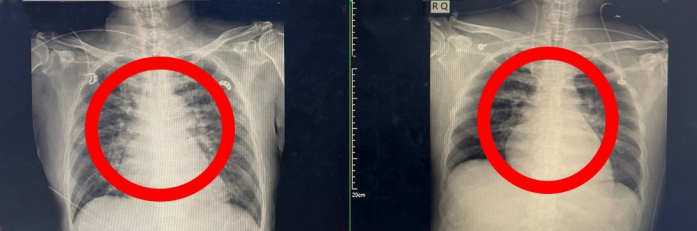

豐原醫院指出,儘管第一時間已給予抗病毒藥物及呼吸與循環支持治療,患者仍出現心因性休克徵象,心肺功能持續惡化,心臟外科隨即決定啟動葉克膜(ECMO)治療,以暫時替代心肺功能,維持全身血液循環與氧氣供應,爭取黃金搶救時間。

在葉克膜支持下,心臟內科張偉俊醫師立即安排緊急心導管檢查,歷時7小時完成高難度冠狀動脈鈣化旋磨與震波氣球治療(Rota-Shock策略),成功打通三條嚴重阻塞之冠狀動脈並完成支架置放,同步放置主動脈內氣球幫浦(IABP),以提升心臟輸出量、減輕心臟負荷並穩定血流動力。

同時患者也因休克引發腎衰竭,腎臟科亦即刻介入,啟動連續性靜脈血液過濾術(CVVH),透過24小時持續性血液淨化治療,協助維持體液與電解質平衡、改善代謝性酸中毒狀態,並降低多重器官衰竭風險,為後續器官功能恢復爭取寶貴時間。